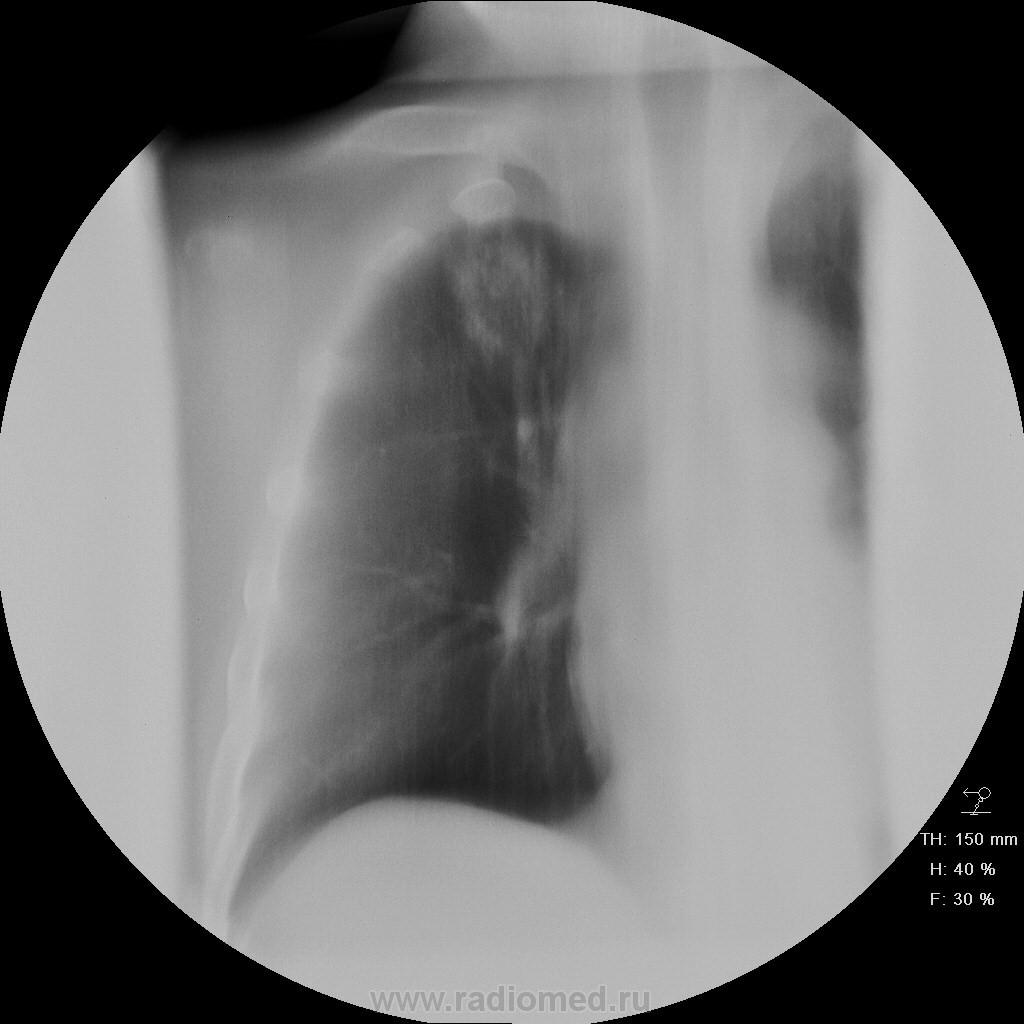

Пациет 60 лет после перенесения ОНМК. жалоб нет ( по легким) . СОЭ, лейкоциты, HB в норме.

Какие будут мнения.

КТ еще не запущен - так что выжимаем все из линейки...

У больных с последствиями ОНМК следует думать об аспирационном генезе заболевания. В пользу этого свидетельствует поражение задних сегментов и двусторонняя локализация изменений.